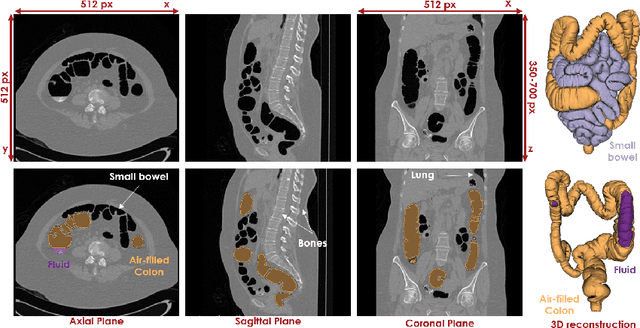

Abstract:High-resolution colon segmentation is crucial for clinical and research applications, such as digital twins and personalized medicine. However, the leading open-source abdominal segmentation tool, TotalSegmentator, struggles with accuracy for the colon, which has a complex and variable shape, requiring time-intensive labeling. Here, we present the first fully automatic high-resolution colon segmentation method. To develop it, we first created a high resolution colon dataset using a pipeline that combines region growing with interactive machine learning to efficiently and accurately label the colon on CT colonography (CTC) images. Based on the generated dataset consisting of 435 labeled CTC images we trained an nnU-Net model for fully automatic colon segmentation. Our fully automatic model achieved an average symmetric surface distance of 0.2 mm (vs. 4.0 mm from TotalSegmentator) and a 95th percentile Hausdorff distance of 1.0 mm (vs. 18 mm from TotalSegmentator). Our segmentation accuracy substantially surpasses TotalSegmentator. We share our trained model and pipeline code, providing the first and only open-source tool for high-resolution colon segmentation. Additionally, we created a large-scale dataset of publicly available high-resolution colon labels.